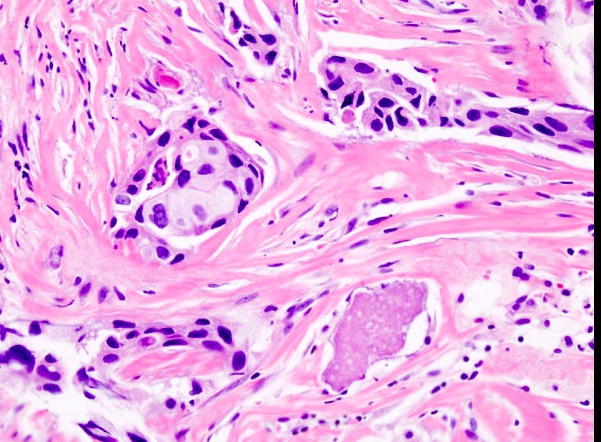

Biopsy of the breast tissue will demonstrate necrotic fat with associated calcification and giant cells.

_sclerosing adnosis, fat necrosis, DCIS..